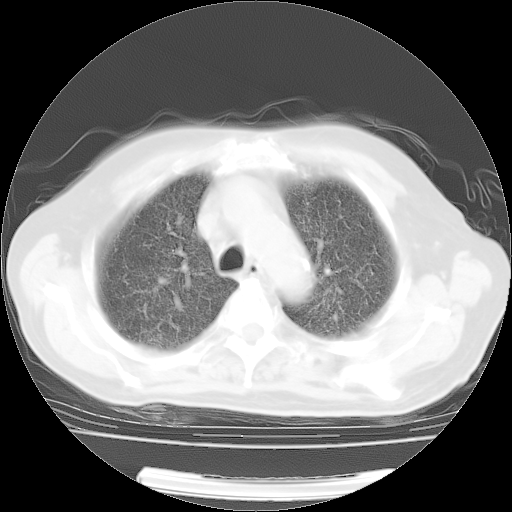

4月14日肺部CT

肺部CT平扫未见异常。